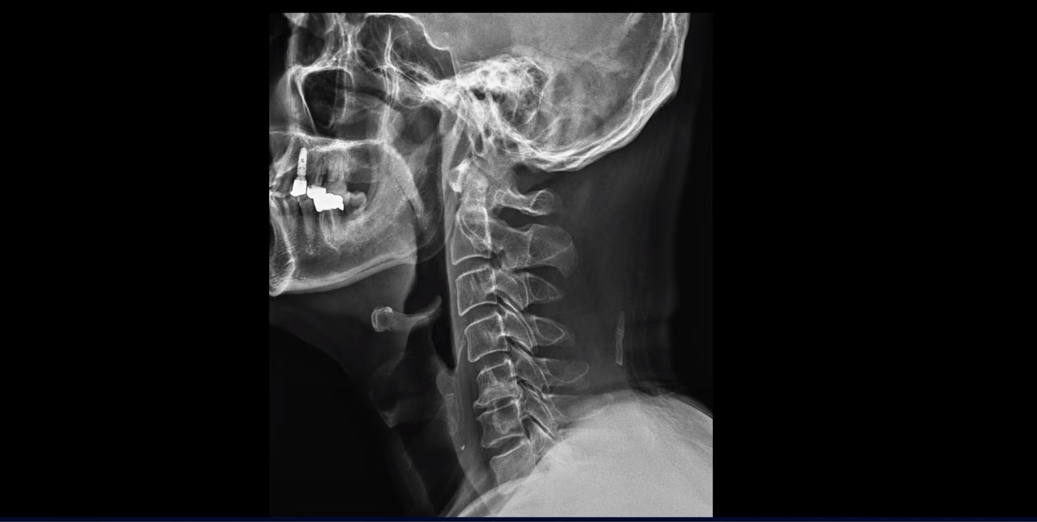

우선 이분 증상은 좌측 어깨와 팔 통증입니다. 이분 MRI를 보면 5번 6번과 6번 7번이 안 좋아 보입니다.

5번 6번에는 오른쪽과 왼쪽 모두 디스크 파열이 있고,

6번 7번에는 왼쪽으로 디스크가 밀려 나와 있습니다.

왼쪽으로 신경이 빠져나가는 추간공을 보면 보시다시피 5번 6번과 6번 7번 신경 구멍이 아래나 위에 비해 막혀있는 게 보입니다.

디스크도 밀려 나와 있고 협착도 있는 겁니다.

이분 왼쪽 어깨와 팔 통증이 갑자기 생긴 이유는 5번 6번 디스크 또는 6번 7번 디스크가 갑자기 밀려 나온 것이 원인일 것으로 보이는데, 그럼 이 디스크들이 밀려 나와서 신경을 자극하거나 누르는데 어떻게 이게 수술 없이도 좋아질 수 있는 걸까요?

이분 목 x-ray를 보시면 일자목이고 이런 목 형태에서는 목 주변 근육이 만성적으로 뭉치고 굳어 있을 수밖에 없습니다.